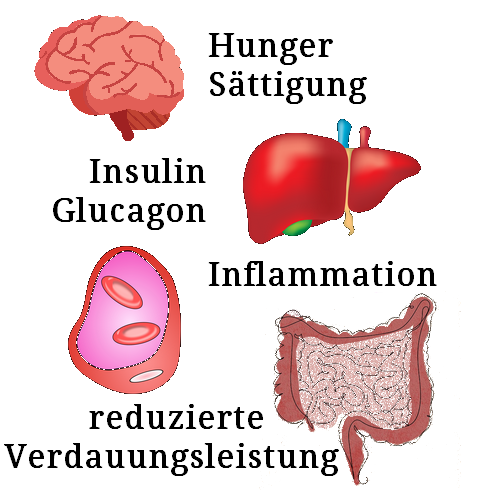

Semaglutid, ein GLP-1-Rezeptor-Agonist (Glucagon-like Peptide-1), wirkt auf Hunger und Sättigung, verlangsamt die Magenentleerung, reguliert den Blutzucker und reduziert Inflammation. (Quelle: Gelbe Liste)